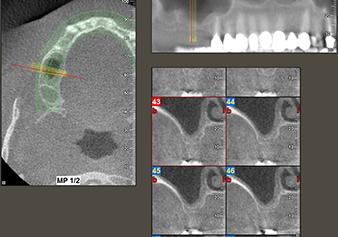

The I2A instrument (diameter 2.0 mm) was then used to perforate the sinus floor intermittently and on the smallest scale possible. This special piezosurgical method ensures that the Schneiderian membrane is not damaged. When the Z25P was used, the membrane was already lifted slightly by the coolant supplied via the instrument tip (Fig. 3). The coolant quantity was just 50% in order to avoid high pressure in the implant bed.

Implant bed preparation and augmentation

Following an intermediate check (Fig. 4) a further preparation step was performed (Fig. 5). Afterwards, the hydraulic Z35P instrument was used to lift the membrane to the desired position (Fig. 6 and 7). This was followed by further piezosurgical preparation of the implant bed, concluded with a rotary bur and shoulder milling cutter up to the implant diameter of 4.8 mm. Before the implant was inserted, the augmentation material (particle size approx. 0.8-1.6 mm) was introduced underneath the Schneiderian membrane (Fig. 8).